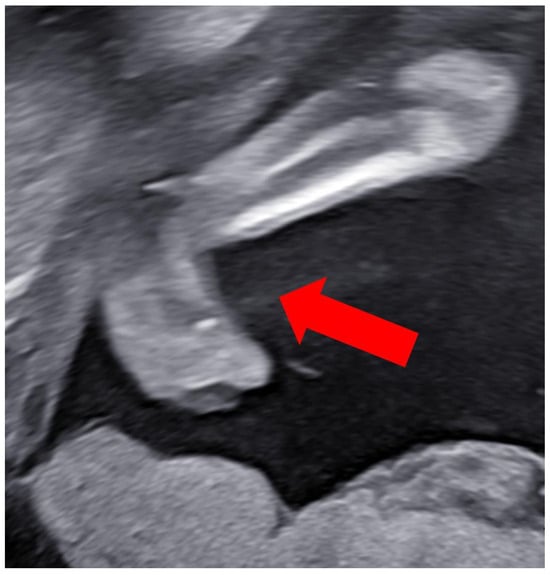

Case Report